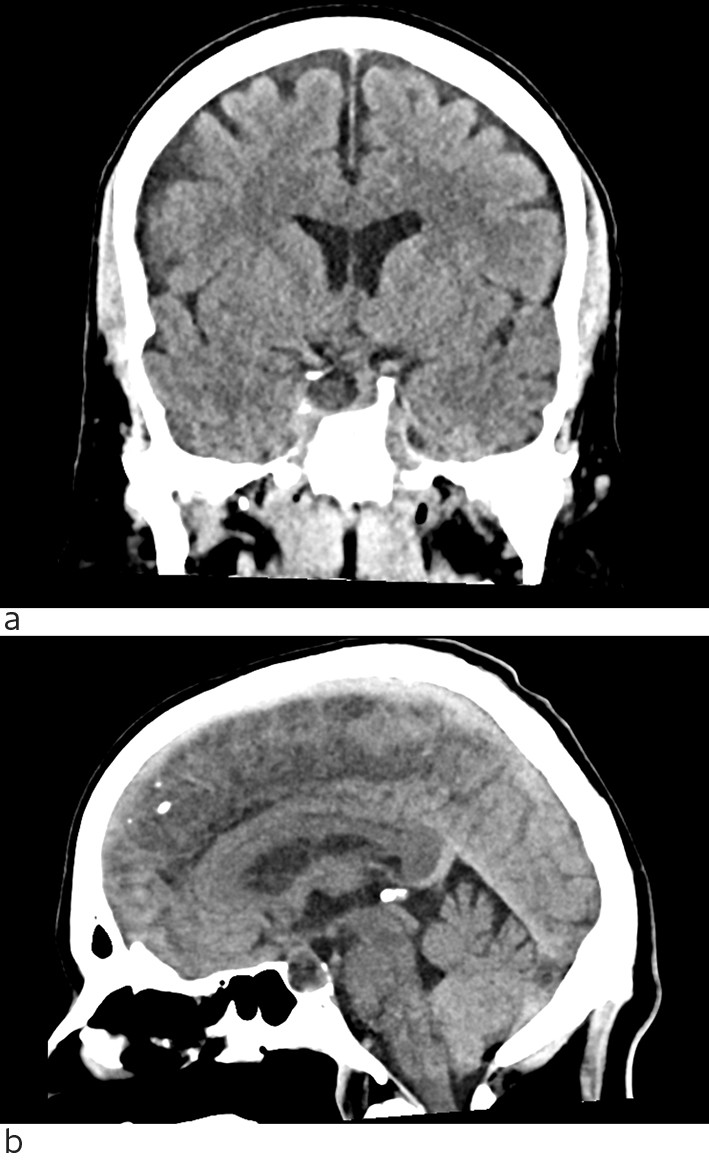

A repeat scrutiny of the head CT scan carried out on admission revealed a low-attenuation lesion in the pituitary gland (Fig. 2). An emergency head MRI scan showed haemorrhage in a pituitary adenoma with a bulge into the cavernous sinus on the right side and affection of the abducens nerve. There was expansion of the sella turcica with absent right lateral wall and pronounced thinning of the posterior wall, which was consistent with an adenoma that had developed over a long period of time with remodelling of surrounding bone. There were also some non-specific lesions in the white matter. The patient was transferred the same evening to the Department of Neurosurgery at Oslo University Hospital. He underwent surgery the following day, with transsphenoidal resection of the pituitary tumour and haemorrhage.

Figure 2 Head CT without intravenous contrast medium. a) coronal section, b) sagittal section. Expansive lesion in sella…

Figure 2 Head CT without intravenous contrast medium. a) coronal section, b) sagittal section. Expansive lesion in sella turcica with expansion into the cavernous sinus on the right side. The tumour extends up to the optic chiasm. Remodelling of adjacent bone structures.